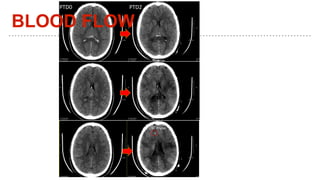

This document discusses using physiology as a target for treating traumatic brain injury (TBI). It summarizes key physiological parameters that should be monitored and targeted in TBI patients, including intracranial pressure (ICP), mean arterial pressure (MAP), partial pressure of brain tissue oxygen (PbtO2), cerebral blood flow (CBF), glucose levels, ventilation, and temperature. Maintaining these physiological markers within certain ranges can help optimize brain mechanics, metabolism and function for TBI patients.